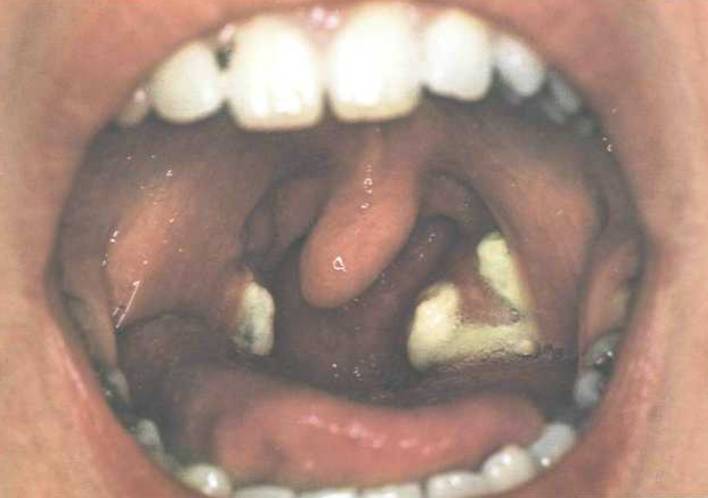

Ангина при инфекционном мононуклеозе

На начальной стадии ангины при инфекционном мононуклеозе определить этиологию ангины по внешнему виду зева невозможно. Через некоторое время на миндалинах появляется белый налет. Миндалины и язычок гиперемируются и отекают. С течением болезни островки сливаются, образуя толстые белые бляшки. Налеты могут сохраняться 1-2 недели и даже дольше, порой сплошь покрывая обе миндалины; общее состояние при этом не страдает. В наиболее тяжелых случаях отек и массивные налеты на миндалинах создают угрозу асфиксии. Внешний вид зева в этом случае резко изменен: толстый налет выходит за пределы миндалин и полностью скрывает язычок.

При такой картине инфекционный мононуклеоз можно спутать только с дифтерией. В пользу инфекционного мононуклеоза говорит спленомегалия, генерализованное увеличение лимфоузлов, обнаружение гетерофильных антител и атипичных мононуклеаров. В отсутствие условий для лабораторных исследований вводят противодифтерийный антитоксин.